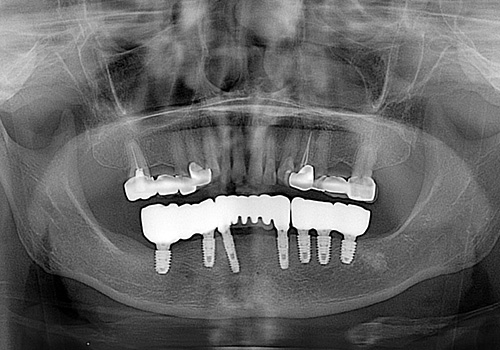

김○근님 임플란트 식립 후

2023년 6월 -